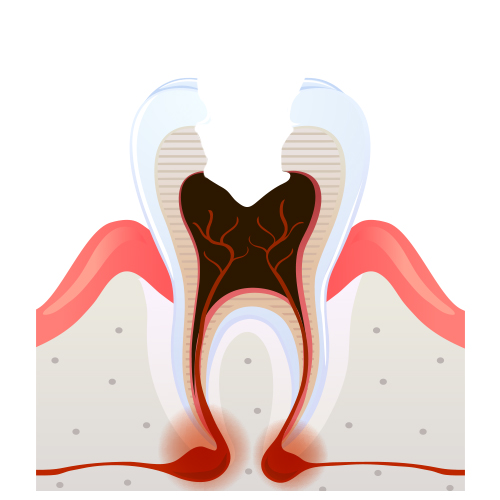

충치의 단계 및 치료법

4단계

뿌리끝까지 진행 뿌리끝에 고름집 형성